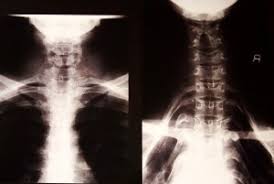

A simple vista parecen cuellos largos pero la verdad es otra, existen radiografías realizadas a las mujeres de esta etnia y en ninguna impresión radiográfica se nota una separación entre las vertebras del cuello, mas bien es el empuje hacia abajo de hombros, clavícula y costillas las que generan este efecto visual, aquí abajo la imagen.